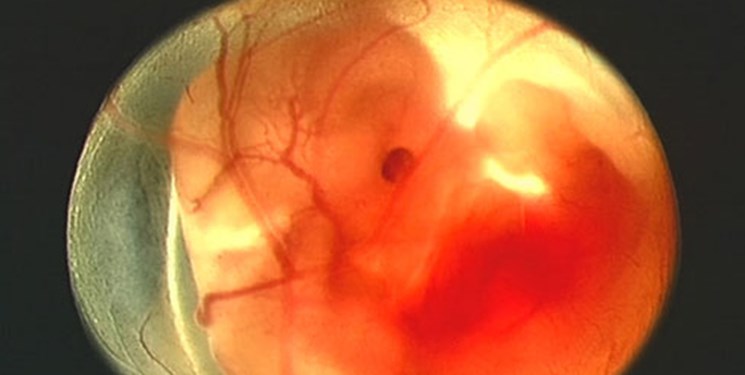

به گزارش خبرنگار گروه علمی و دانشگاهی خبرگزاری فارس، پرده آمنیوتیک داخلی ترین لایه مجاور مایع آمنیوتیک و جنین است ضخامت آن در حد میلی متر است.